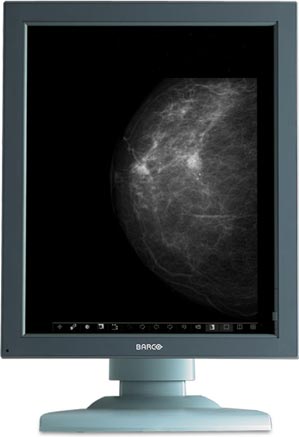

Διαγνωστικές οθόνες υψηλής ευκρίνειας

Οι σύγχρονες εφαρμογές απεικονιστικών ιατρικών διαγνώσεων απαιτούν εξαιρετικής ποιότητας μηχανήματα και οθόνες διάγνωσης, για την απόλυτη απεικόνιση των αποτελεσμάτων.

Η εταιρεία μας προμηθεύει τις υπερυψηλής ευκρίνειας οθόνες για ιατρικά μηχανήματα, της εταιρείας Barco.